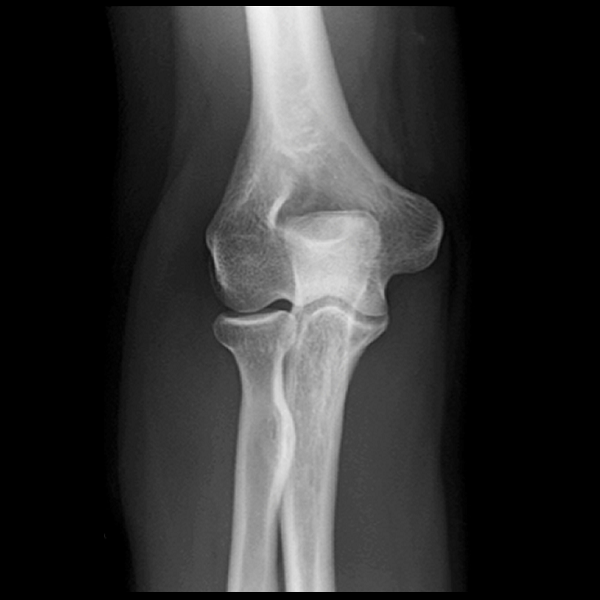

Learn the bony anatomy then test yourself